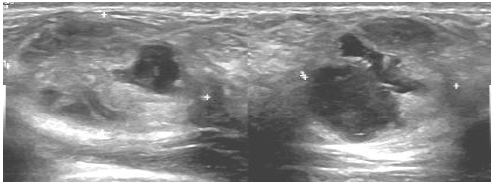

Paciente puérpera com 33 anos, informa que há duas semanas, durante amamentação, palpou um nódulo na mama direita.

O achado encontrado no exame de imagem classifica-se como: